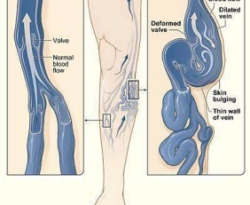

Home Remedies for Varicose Veins

In our body there is a huge network of veins, which carry blood from one part of the body to the other part. When some injury happens to even a single vein, the blood flow gets affected. This can further lead to several diseases. Many times the veins get congested due to the blood clots […] Read More- By ZColonHealth